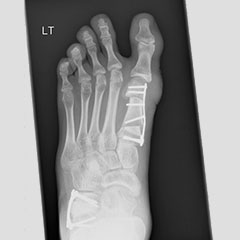

Hallux Valgus (Bunions)

Bunions can occur in children and adults. Juvenile hallux valgus is the name for a bunion that develops during childhood. No one knows with certainty why juvenile hallux valgus occurs.

Juvenile hallux valgus causes a bump on the inside of the foot at the base of the great toe and some children are very sore around it.

Children and teens with bunions should wear shoes with a wide toe box and low heels so they don't put too much pressure on the bump or make the condition worse. Orthotics and physiotherapy may help, particularly in children with flat feet.

Surgery should only be considered for children who have persistent, significant pain which gets in the way of activities, even after trying non-surgical treatment.

There are several surgical procedures used to correct this deformity; much of the surgical decision making depends on how the foot looks on physical exam and x-ray.

Flat foot - before

Flat foot - after